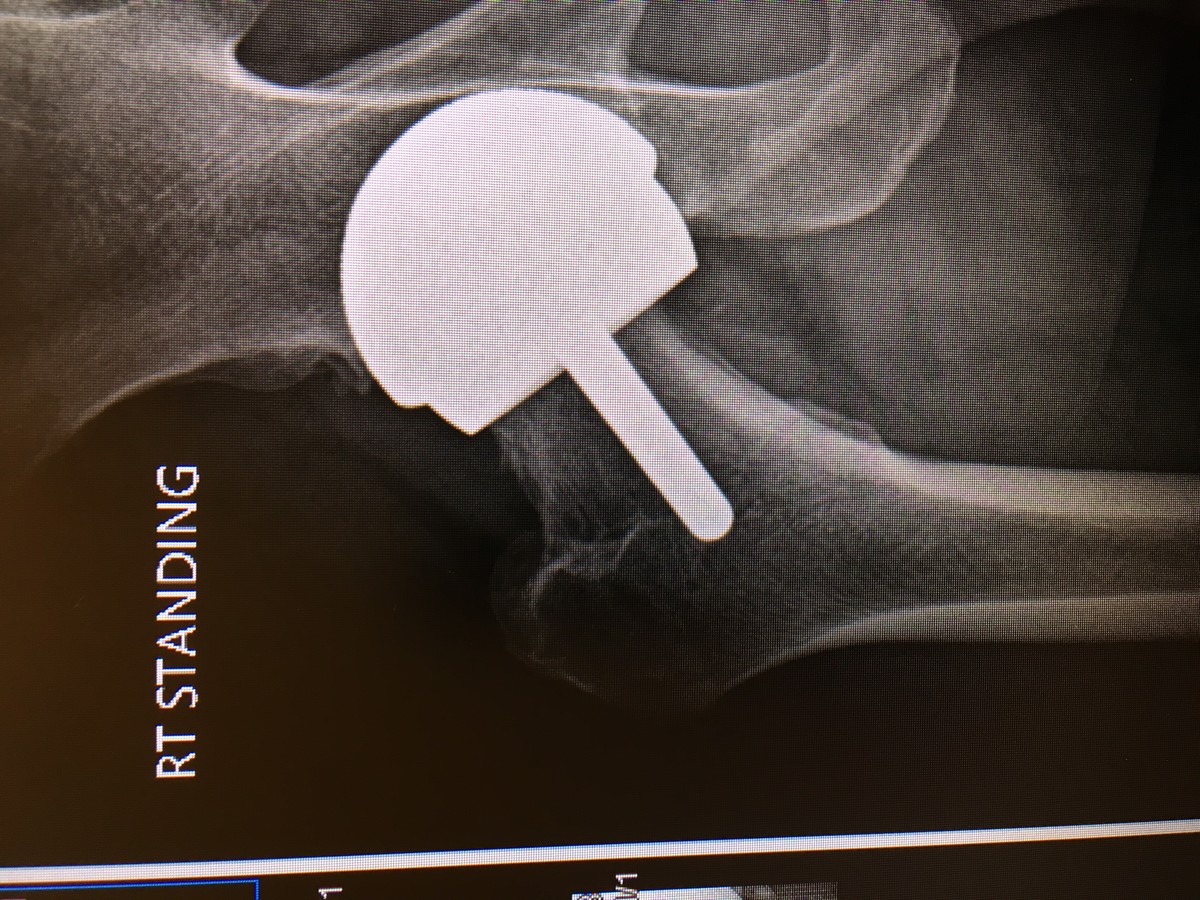

Back in the Saddle Horse Riding After a Hip Replacement

Horseback Riding After Direct Anterior Hip Replacement on Vimeo Horse Back Riding After Hip Replacement It is generally recommended to avoid riding a horse after hip replacement surgery. Horseback riding after joint replacement. The high impact and risk of falls associated with horseback riding can put stress on the hip joint and potentially cause damage. I recently underwent total hip replacement of my left hip and am anxious to return to horseback riding during my. Horse Back Riding After Hip Replacement.